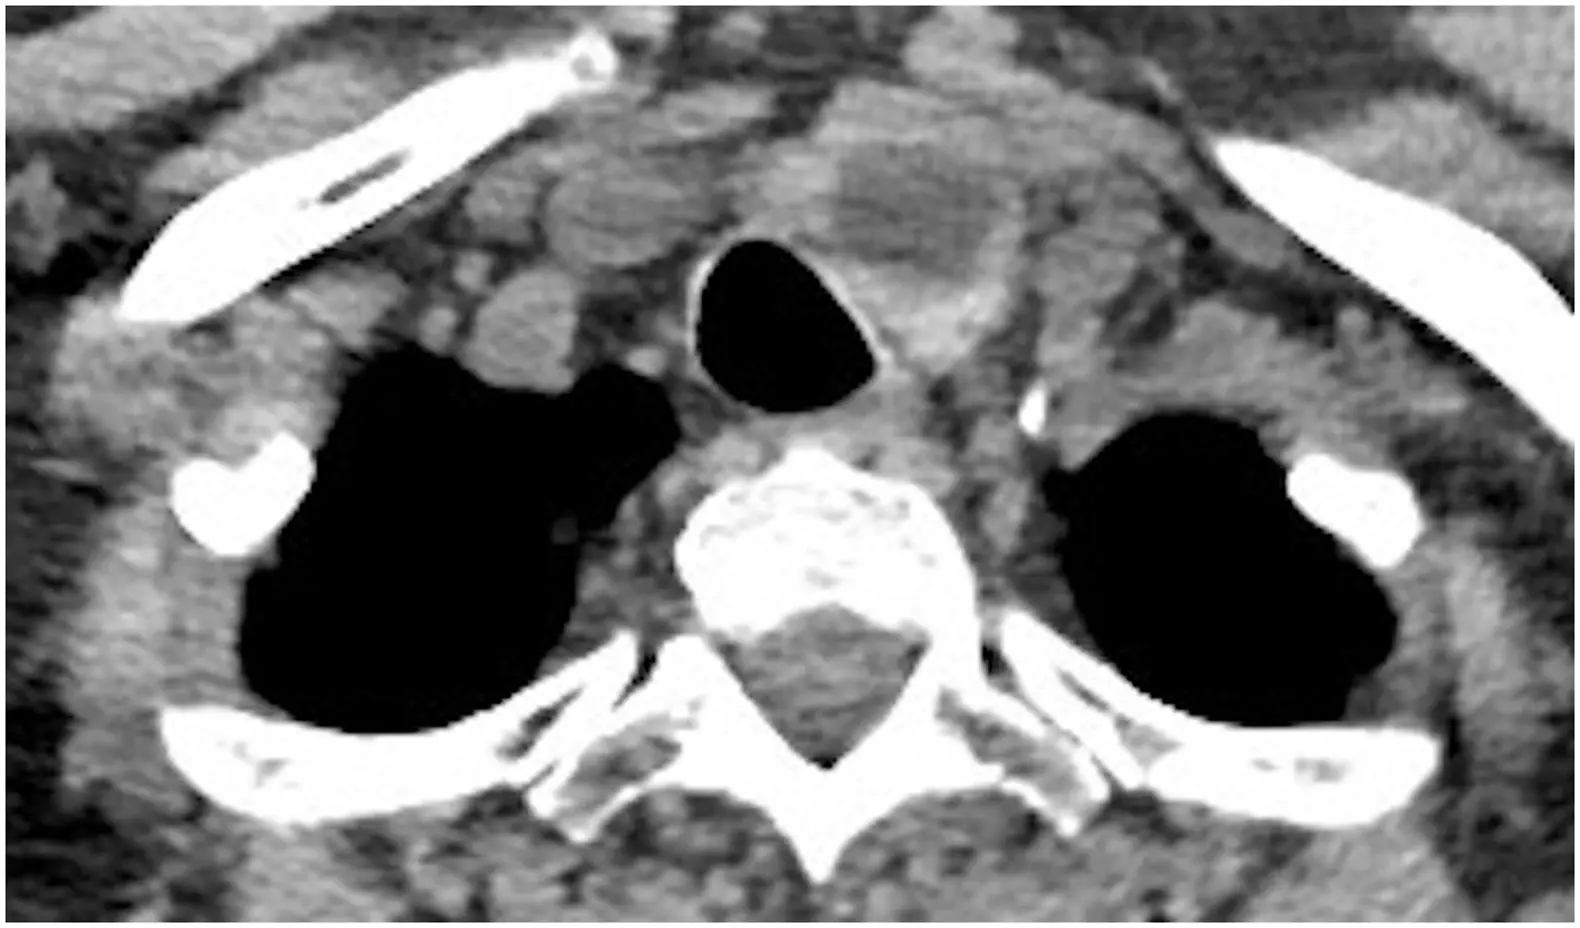

Normal CT appearance of the thyroid gland: (Source)

Non-contrast axial CT images (A) shows a normal hyperdense thyroid gland relative to the adjacent skeletal muscles. Contrast axial (B) and coronal (C) images shows intense enhancement of the thyroid gland.